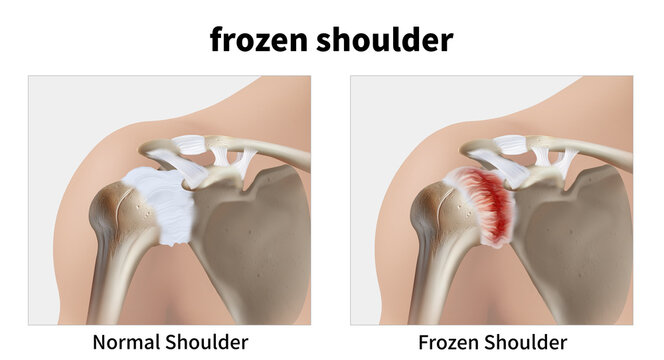

Frozen Shoulder